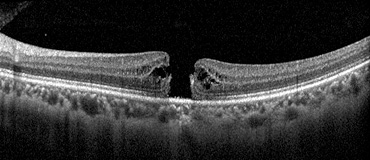

황반원공 수술 전

황반원공 수술 후15년간 대학병원에서 많은 환자들을 진료하고 수술한 경험과 지식을 토대로 환자분들께 최선을 다해 맞춤형 수술을 시행하고,